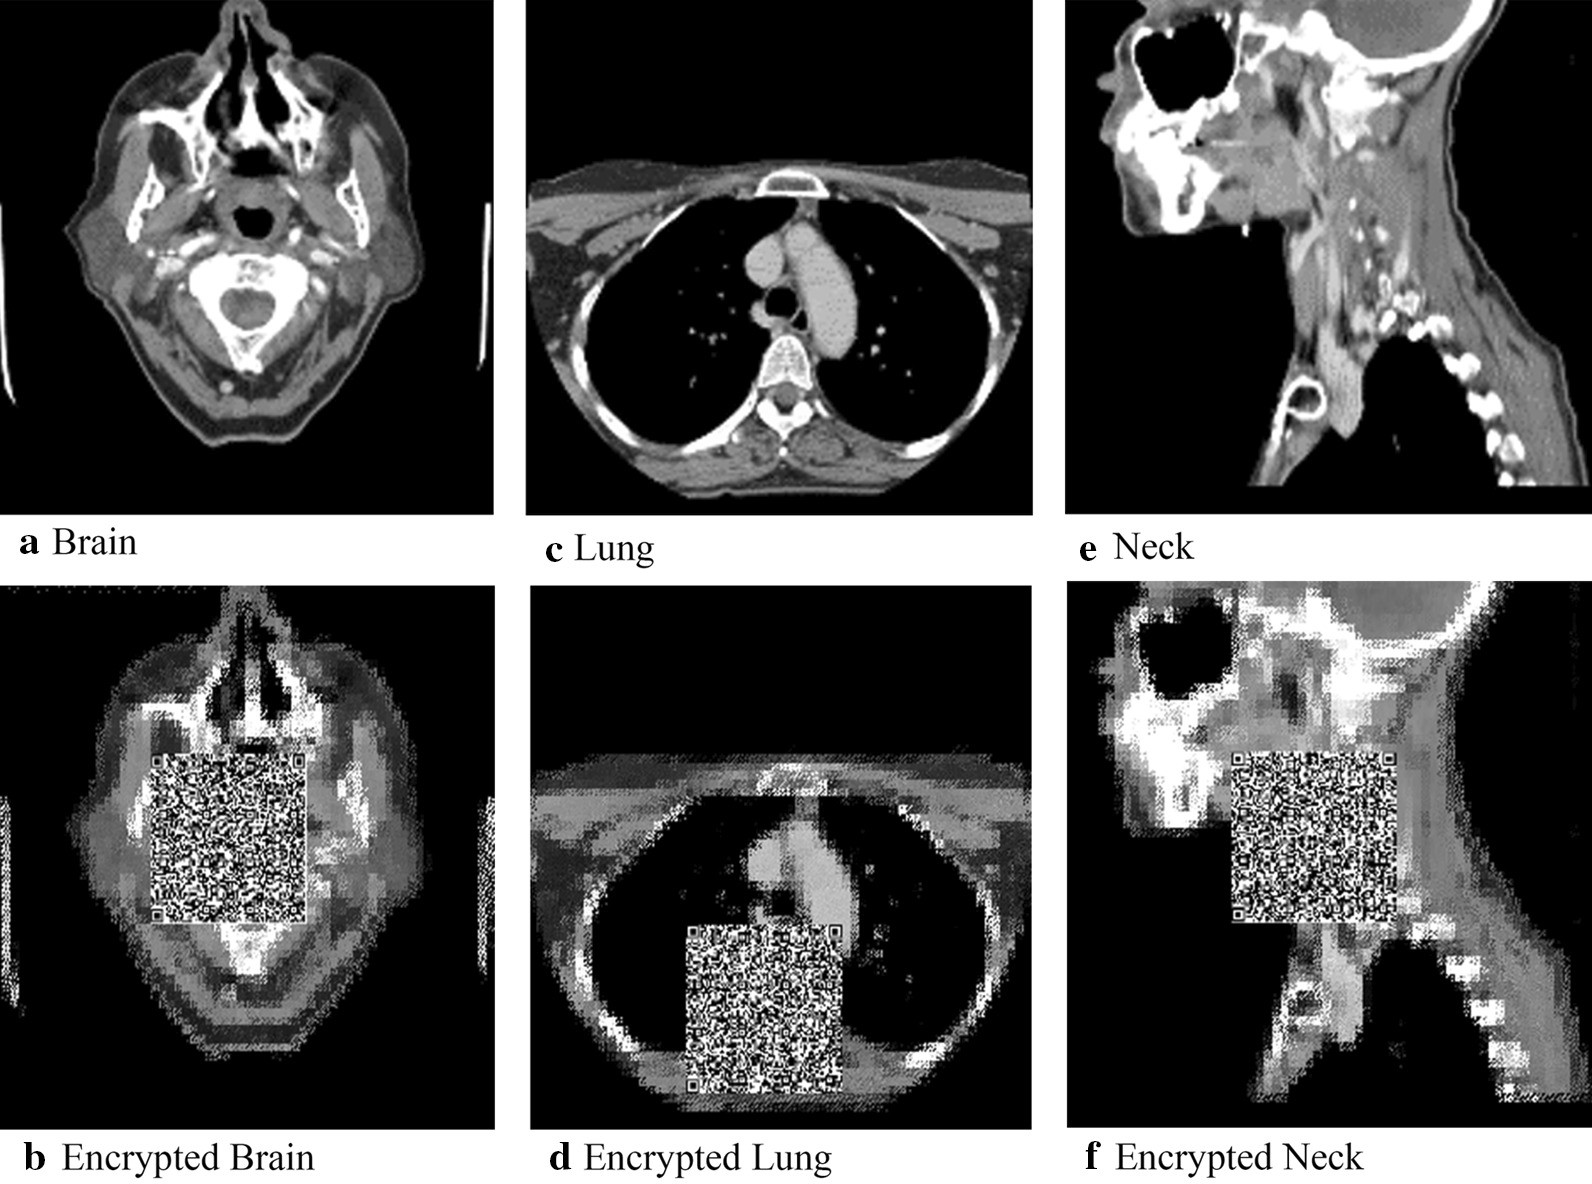

Fig. 4From: A partial encryption algorithm for medical images based on quick response code and reversible data hiding technologyExamples of original and encrypted imagesBack to article page